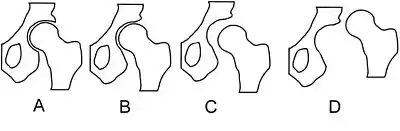

Hip dysplasia can range from barely detectable to severely malformed or dislocated. The congenital form, teratologic or non-reducible dislocation occurs as part of more complex conditions.

In acetabular dysplasia, the acetabulum (socket) is too shallow or deformed. The center-edge angle is measured as described by Wiberg.[6] Two forms of femoral dysplasia are coxa vara, in which the femur head grows at too narrow an angle to the shaft, and coxa valga, in which the angle is too wide.

Some sources prefer the term "hip dysplasia" over DDH, considering it to be "simpler and more accurate", partly because of the redundancy created by the use of the terms developmental and dysplasia.[41] Types of DDH include subluxation, dysplasia, and dislocation. The main types are the result of either laxity of the supporting capsule or an abnormal acetabulum.